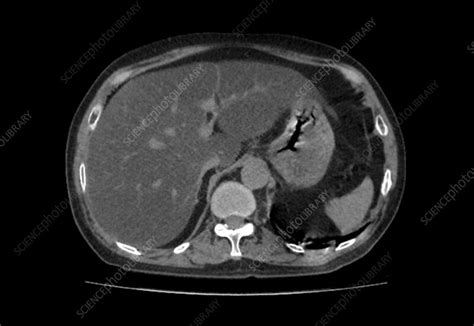

Unlocking Fatty Liver: Your CT Scan Guide Hey guys, ever heard the phrase ‘fatty liver’ and wondered what it truly means, especially when your doctor mentions a CT scan ? You’re definitely not alone! It’s a super common condition, often silent and sneaky, but understanding it is a huge step towards better health. Think of your liver as one of your body’s unsung heroes – it’s always busy detoxifying, producing proteins, and helping with digestion. When it starts accumulating too much fat, that’s when we call it fatty infiltration of the liver , or medically, hepatic steatosis . It’s a condition that can range from a mild, almost harmless state to something more serious if left unchecked, potentially progressing to inflammation, scarring, and even cirrhosis . That’s why getting a clear diagnosis and understanding what’s going on inside is so important. And this is where a CT scan really shines as a key diagnostic tool. This article is all about demystifying the CT scan process, explaining what your doctor is looking for, and helping you understand what your results might mean. We’ll dive into the nitty-gritty of how these scans work to detect fatty liver , what those fancy medical terms like ‘Hounsfield Units’ actually refer to, and why a comparison to your spleen might be relevant. Our goal here is to empower you with knowledge, making sure you feel informed and ready to discuss your liver health with your healthcare provider. So, let’s pull back the curtain on fatty liver and CT scans together, ensuring you have the lowdown on taking control of your well-being. Getting to grips with how medical imaging can reveal important insights about your internal organs, especially something as vital as your liver, is incredibly beneficial for anyone navigating their health journey. We’re going to break down complex medical jargon into easy-to-digest info, making sure you feel confident and prepared for those conversations with your doctor. Understanding the diagnostic tools available, like the CT scan , can truly make a difference in how you approach your overall liver health and the steps you take towards a healthier future. So buckle up, because we’re about to make understanding your liver and its health a whole lot clearer! We’ll cover everything from what causes fatty liver to what you can do about it, all through the lens of how a CT scan helps paint that crucial picture. This journey of understanding begins now, and it’s all about equipping you with the best information to advocate for your own health. Ready? Let’s go! # What Exactly is Fatty Liver, Anyway?Alright, let’s start with the basics. What exactly is fatty liver , also known as hepatic steatosis ? Simply put, it’s a condition where too much fat builds up in your liver cells. Now, having a tiny bit of fat in your liver is totally normal, guys. Your liver is a busy organ, involved in practically everything from processing nutrients to filtering toxins. However, when fat accounts for more than 5-10% of your liver’s weight, that’s when we officially call it fatty infiltration of the liver . This isn’t just some abstract medical term; it represents a real change in how your liver functions and looks. The scary part? Often, fatty liver doesn’t cause any noticeable symptoms in its early stages. You might not feel a thing, which is why it’s sometimes called a silent disease. But don’t let its quiet nature fool you; it’s a condition that warrants attention. There are two main types of fatty liver : alcoholic fatty liver disease (AFLD), caused by heavy alcohol consumption, and non-alcoholic fatty liver disease (NAFLD), which, as the name suggests, isn’t linked to alcohol. NAFLD is incredibly common, affecting about one-quarter of the global population, and its prevalence is rising rapidly alongside rates of obesity, type 2 diabetes, and metabolic syndrome. If you’ve ever heard of conditions like high blood pressure, high cholesterol, or insulin resistance, these are often buddy-buddy with NAFLD. The progression of NAFLD can be concerning. While simple fatty liver (steatosis) is generally considered benign, it can progress to non-alcoholic steatohepatitis (NASH), where inflammation and liver cell damage occur alongside the fat. This inflammation can lead to fibrosis (scarring), which, if severe enough, can turn into cirrhosis – a serious, irreversible form of liver damage that can impair liver function and even lead to liver failure or liver cancer. Understanding this potential progression is crucial for appreciating why early detection and management of fatty infiltration of the liver are so vital. It’s not just about seeing fat; it’s about preventing a cascade of more severe liver disease . This understanding sets the stage for why tools like the CT scan are so important in diagnosing and monitoring this condition. We’re talking about taking proactive steps to safeguard one of your most critical organs, and it all starts with recognizing what fatty liver is and why it matters to your overall health. It’s truly a journey towards better liver health , and knowing the enemy is the first step in winning the battle. So, when your doctor mentions fatty liver , remember it’s a signal to pay attention to your lifestyle and well-being. # The Role of CT Scans in Diagnosing Fatty Liver Okay, so we know what fatty liver is. Now, let’s talk about how we actually see it. This is where the mighty CT scan comes into play. You might be wondering,